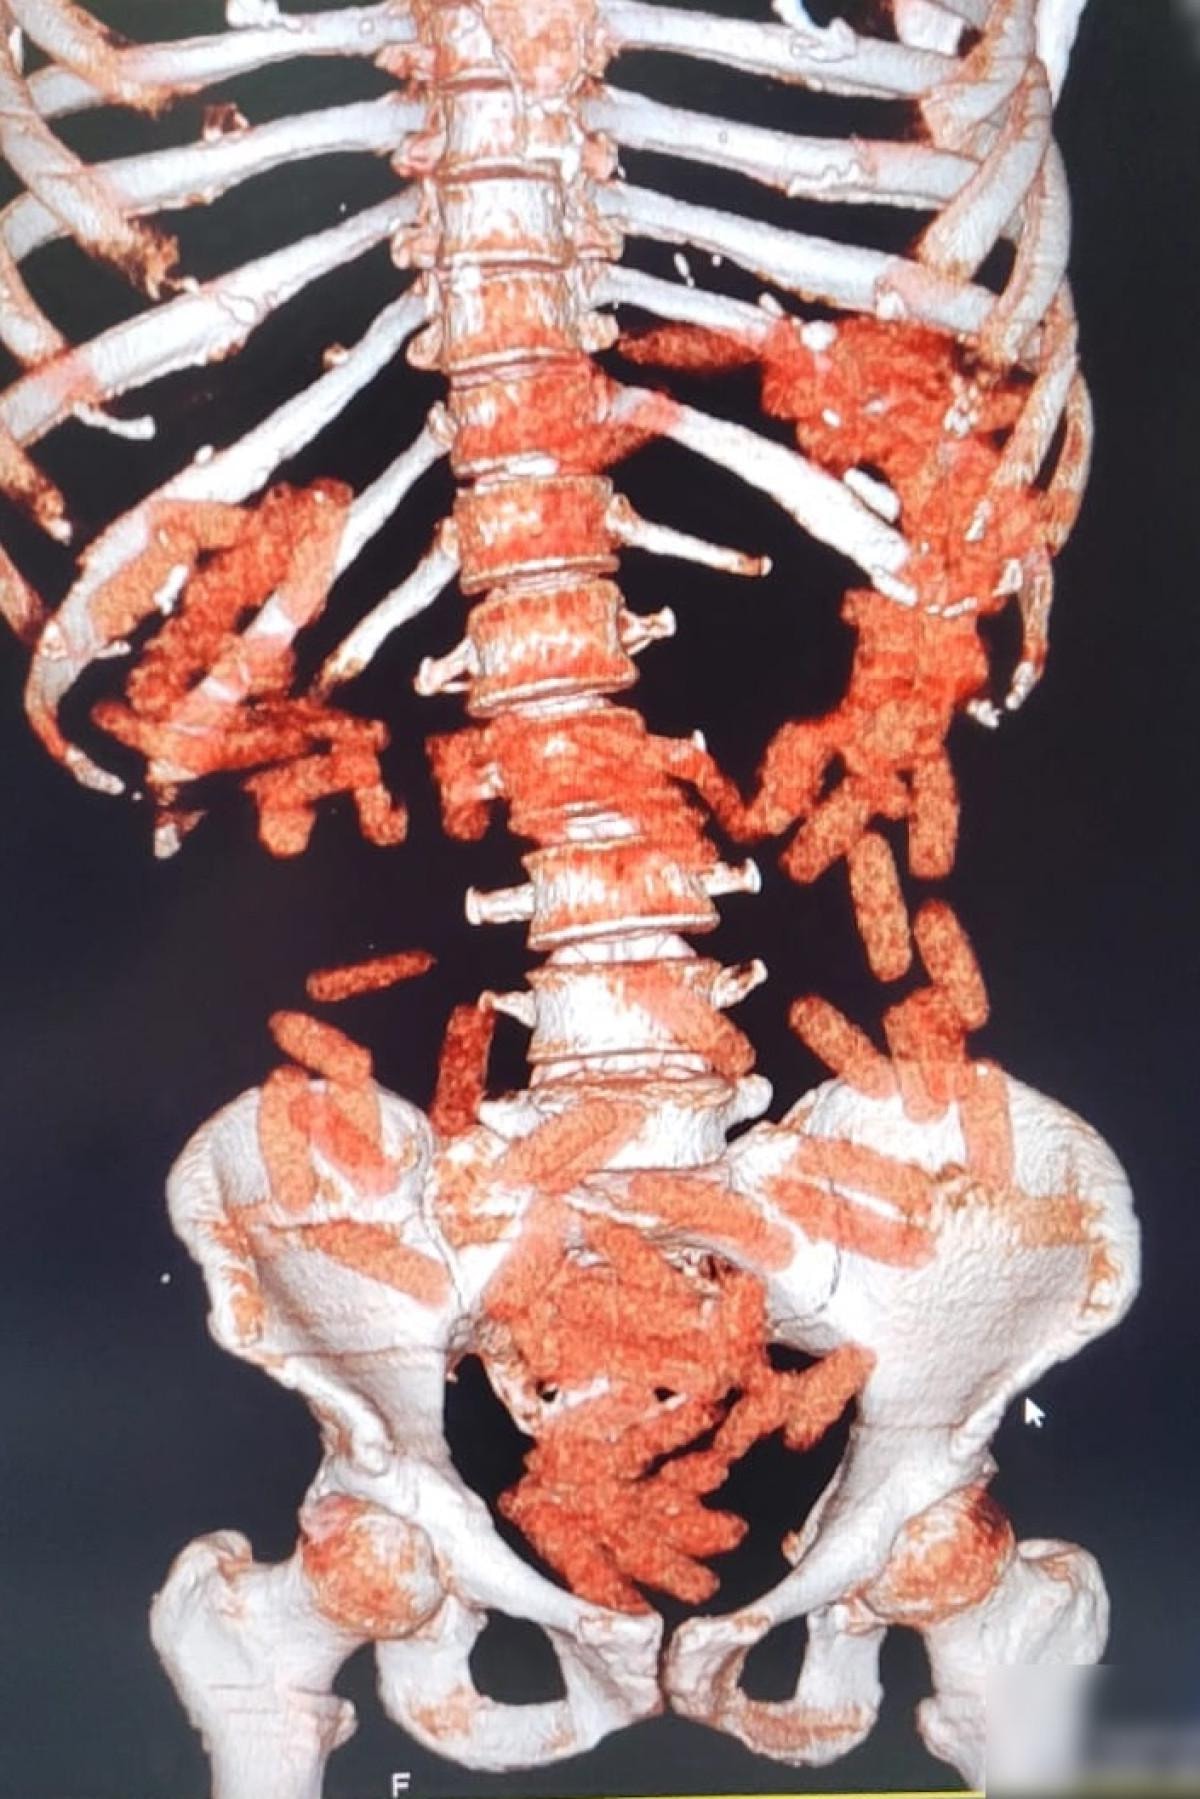

Gözaltına alınan A.G.'nin röntgen ve tomografi görüntülerinde midesinde uyuşturucu bulunduğu belirlendi. Gerçekleştirilen ameliyat sonucunda, şüphelinin midesinden 88 kapsül halinde toplam 974,52 gram afyon sakızı çıkarıldı. A.G., taburcu edildikten sonra her iki şüpheli "uyuşturucu madde ticareti" suçlamasıyla mahkemeye sevk edilerek tutuklandı.